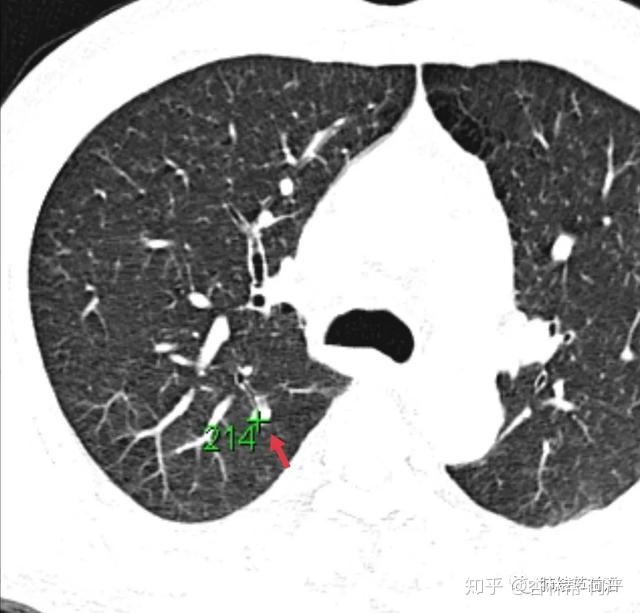

结节1:CT值为197,诊断为纤维灶结节。

结节2:CT值为214,诊断为纤维灶结节。

这三例结节测CT值后,均接近200或高于200。对于这样的结节,基本可以排除肺癌。可以放心随访,大大减轻患者的焦虑(随访的间期对很多人来说是极大的煎熬)。第一次3-6个月,以后6-12月复查,三年完全排除肺癌。